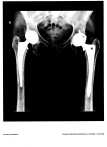

I began to think about the “Zimmer” appliance I will have installed in me and how funny it would be to incorporate that conversation in Hipster Meetings….are you a “Stryker, Johnson & Johnson, Wright or Zimmer” Hipster?  We’d be wearing name tags with our appliance name under our own….  🙂

August 9, 2008On July 24, 2008.   Zimmer Holdings, the nation’s largest producer of orthopedic devices, announced the suspension of sales of an artificial hip implant component due to a high failure rate. The medical device, a hip socket known as the Durom cup, was first sold in the U.S. in 2006 and has been implanted in 12,000 patients.  YOUNG PATIENTS.  Kind of defeats the purpose doesn’t it, when you never fully heal before the pain begins again.

Jodi is a DOUBLE HIPster with a “Zimmer” in her left hip and ceramic in her right.  Bionic woman of the 21st century, Jodi has used both THR approaches – the left hip was the posterior cutting through the muscle  (ouch) and in the right hip almost three years later, she used the anterior approach, which is a weaving through the muscles and ligaments.